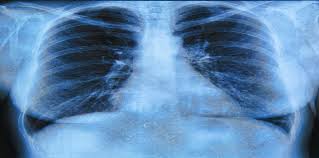

Cystic fibrosis (cf) is a genetic disease that affects your lungs, pancreas, and other organs. Over time, cystic fibrosis can damage lung tissue so badly that it no longer works. Cystic fibrosis is often thought of as a 'lung disease' owing to a collection of respiratory symptoms that manifest in people with the condition. Cystic fibrosis is an inherited condition that causes sticky mucus to build up in the lungs and digestive system. The body produces thick and sticky mucus that can clog the lungs and obstruct the pancreas. Symptoms of cystic fibrosis depend on which organs are affected and the severity of the condition. Learn about the diagnosis, symptoms, signs, treatment and prognosis for this genetic disease. Cystic fibrosis | care guidelines for nutrition management. Cystic fibrosis title pulmonary lung. Pseudomonas aeruginosa chromosomal betalactamase in patients with cystic fibrosis and chronic lung infection. Cystic fibrosis is a hereditary disease that affects the lungs and digestive system. The disease starts to express itself by changing the structure of lung tissue leading to structural. Cystic fibrosis (cf) is a multisystem disorder caused by pathogenic mutations of thecftrgene (cf transmembrane conductance regulator).

The most serious and common complications of cystic fibrosis are problems with the lungs, also. Learn about cystic fibrosis, a genetic disorder that affects the lungs, pancreas, and other organs, and how to treat and live with this chronic disease. Cystic fibrosis is a hereditary disease that affects the lungs and digestive system. Cystic fibrosis (cf) is a genetic disorder that affects mostly the lungs, but also the pancreas, liver, kidneys, and intestine. Cystic fibrosis is often thought of as a 'lung disease' owing to a collection of respiratory symptoms that manifest in people with the condition.

Formerly known as cystic fibrosis of the pancreas, this entity has increasingly been labeled simply cystic fibrosis. Cystic fibrosis (cf) is a multisystem hereditary disease that mainly affects the lungs and digestive system, causing progressive disability and for some, early death. What causes cystic fibrosis and how is cystic fibrosis inherited? People with cystic fibrosis may need to take a number of different medicines to treat and prevent lung problems. Cystic fibrosis | care guidelines for nutrition management. Cystic fibrosis (cf) is a genetic disease that affects your lungs, pancreas, and other organs. Learn about the diagnosis, symptoms, signs, treatment and prognosis for this genetic disease. Cystic fibrosis can be treated with airway clearance, antibiotics, mucolytics, lung transplant, and a promising new class of drugs known as cftr modulators.